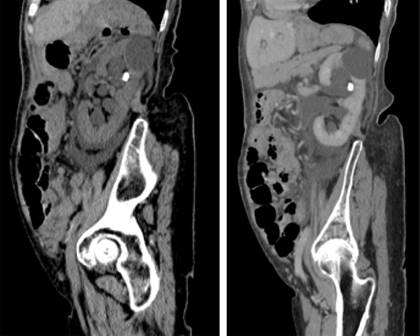

Figura 1: Reconstrucciones sagitales oblicuas de la tomografía y con contraste intravenoso en fase nefrográfica, las cuales muestran pielocaliectasia y lito en sistema calicial superior.